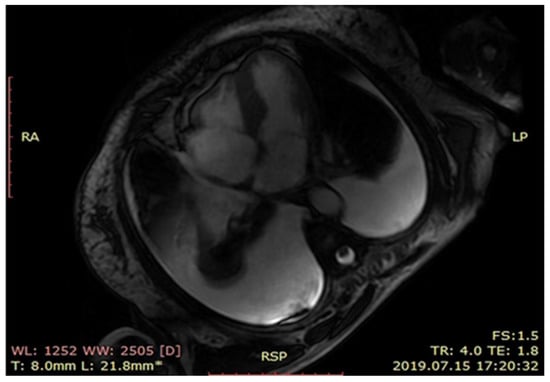

At cardiology department cardiac magnetic resonance (Figure 2) revealed left ventricle hypertrophy mainly concerning intraventricular septum, small ventricle dimensions and late gadolinium enhancement of the left ventricle muscle. Nuclear imaging with radiolabeled phosphonates (99mTc-DPD scintigraphy) was not available during the hospitalization thus to put the diagnosis a myocardial biopsy was done. The endomyocardial biopsy was complicated by a cardiac tamponade and the patient was immediately transferred to the cardio surgery operating theatre. Despite successful surgery, the intensive care unit treatment and an intravenous infusion of levosimendan, the patient died the next day after surgery. The histopathological examination including Congo red staining and evaluation of protein fibers in an electron microscope confirmed the diagnosis of a transthyretin type of amyloidosis (ATTR) (Figure 3A,B).

Figure 2. MRI scan showing left ventricle hypertrophy.